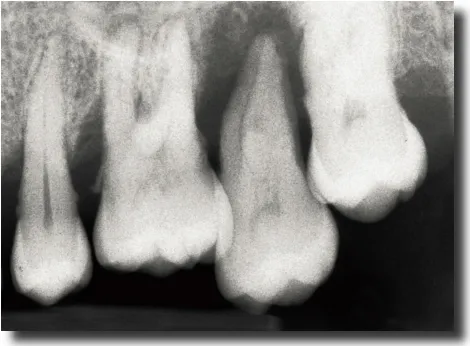

Fig 1-1a Aggressive periodontitis in a 40-year-old woman who is subject to stress and smokes one pack of cigarettes a day. The patient experienced an emotional shock 5 years earlier. A conventional treatment plan was initiated and included periodontal surgery throughout all quadrants. Professional maintenance (scaling and root planing) was carried out every 3 months, and the patient responded well.

Fig 1-1b Four years after treatment and maintenance therapy. Periodontal status has deteriorated in all areas. Observe the new attachment losses, dental migrations, and larger diastemata. It is clear that periodontal disease is not controlled. This patientās disease was refractory to conventional treatment. Specific risk factors in this patient were underestimated.